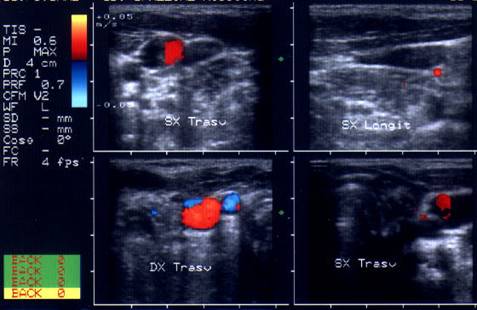

Femeie de 34 ani. Tiroida de dimensiuni normale, de

consistenta dura, cu suprafata neregulata si pseudonodulara, dureros la palpare.

Marginile lobilor sunt rau definite; structura este mult neomogena cu alternanta

de arii hipoecogene d e edem si altele hiperecogene, cu aspect pseudonodular.

Examene de laborator: moderat hipertiroidism; indicii de fiboza mult ridicati.

Aceeasi pacienta. Vascularizatie intraglandulara mult diminuata.